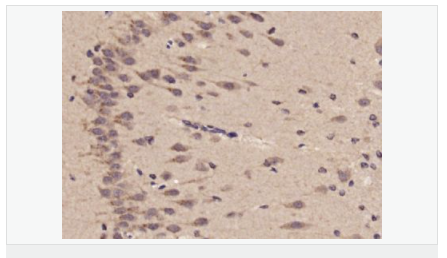

| 產品應用 | WB=1:500-2000 ELISA=1:5000-10000 IHC-P=1:100-500 IHC-F=1:100-500 ICC=1:100-500 IF=1:100-500 (石蠟切片需做抗原修復) not yet tested in other applications. optimal dilutions/concentrations should be determined by the end user. |

| 產品介紹 | This gene is an ortholog of the C. elegans unc-76 gene, which is necessary for normal axonal bundling and elongation within axon bundles. Other orthologs include the rat gene that encodes zygin II, which can bind to synaptotagmin. [provided by RefSeq, Jul 2008] Function: Involved in axonal outgrowth and fasciculation. Subunit: Homodimer; difulfide-linked. May form heterodimers with FEZ1. Interacts with synaptotagmin. Tissue Specificity: Expressed in nonneural tissues, such as heart, lung, spleen, muscle, testis, placenta and melanocytes. Similarity: Belongs to the zygin family. SWISS: Q9UHY8 Gene ID: 9637 Database links: Entrez Gene: 9637 Human Entrez Gene: 225020 Mouse SwissProt: Q76LN0 Human SwissProt: Q9UHY8 Human SwissProt: Q6TYB5 Mouse Unigene: 258563 Human Unigene: 236835 Mouse Unigene: 8714 Rat Important Note: This product as supplied is intended for research use only, not for use in human, therapeutic or diagnostic applications. |